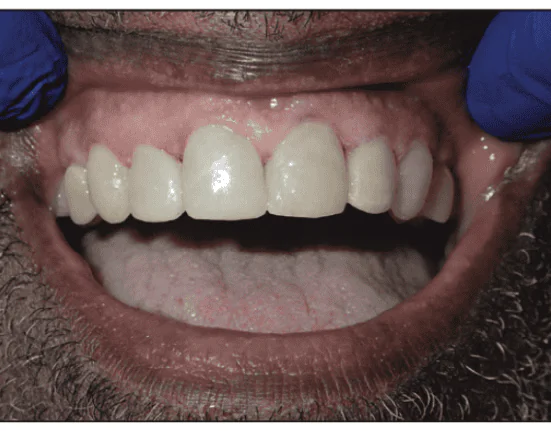

A male in his 60s was seeking to improve his smile, but again, cost was an issue. He wished to close the diastemas and improve the color (Figure 4). Direct composite veneers were diagnosed and approved. Our protocol calls for smile design5 and occlusal analysis6 to ensure durable results that the patient will love, and a wax-up constructed to those specifications. Study models were made using a hydrophilic alginate substitute, Silginat (Kettenbach). Building 6 direct composite veneers freehand with accurate incisal edge position, ideal lingual surfaces, and good occlusion is a daunting task and can easily take several hours; thus, an LA Institute design silicon matrix was fabricated from the ideal wax-up, using Panasil Putty (Kettenbach) only wrapping 1 mm up the incisal edge (Figure 5). Using this matrix accelerates the procedure, as the shape of the lingual surfaces, incisal length, position, and occlusion will be established with the matrix.

OMNICHROMA (Tokuyama Dental America) is a highly sophisticated material with multiple benefits. Its chameleon effect design allows for an unreal color match, with ideal consistency for sculpting, and it is designed to give clinicians time to sculpt even with ambient light. Because of the large diastema, the silicon matrix was used as a guide for minimal preparation while breaking contacts needed for symmetry (Figure 6). All 6 teeth were etched for 25 seconds using Ultra-Etch 35% phosphoric acid (Ultradent) (Figure 7), washed and dried until enamel looked frosted, then primed and bonded all 6 teeth at the same time using Clearfil SE Protect (Kuraray America). OMNICHROMA was used to build the entire missing tooth, including incisal edges, and was applied directly to the silicon matrix, estimating how much material would be needed. The matrix was seated on the mouth, and all teeth were built simultaneously using the matrix as a guide. The matrix allows for an accurate formation of the lingual surfaces, interproximal and incisal edge in a few minutes. The trick is partial curing of the composite, allowing the composite to get hard without maximum hardness, which permits separation of the teeth using a CeriSaw (DenMat) (Figure 8). The facial finishing and interproximal repairs are more artistic and take the longest. After building the entire tooth with OMNICHROMA, which closely matched the color of the patient’s natural teeth, I used a very thin layer of Estelite A1 (Tokuyama Dental America) to lighten the shade a bit. Usually, a 6 direct veneer case should be done in 1.5 hours using this system that was developed and taught at the LA Institute. The patient was extremely satisfied (Figure 9).